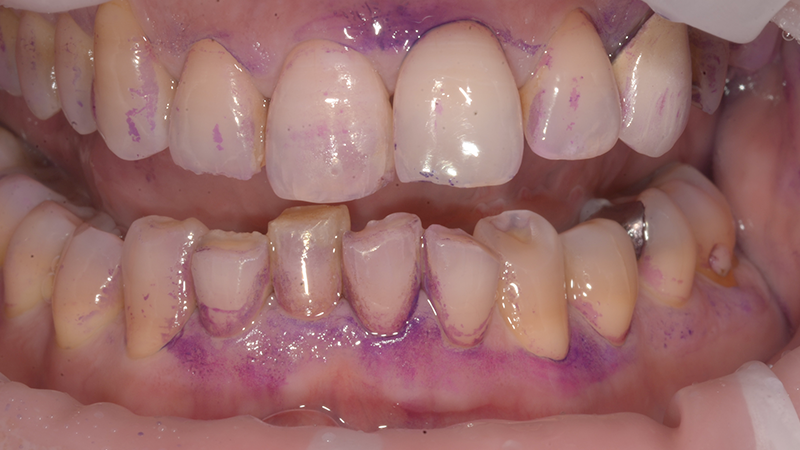

L’igienista dentale, in sinergia con tutto il team, ha il compito di costruire un’alleanza terapeutica efficace, informando il paziente e supportandolo nel controllo quotidiano dei fattori di rischio. Strumenti come la videocamera intraorale, i rivelatori di placca e la documentazione fotografica diventano alleati indispensabili per far “vedere” al paziente la malattia e aumentare la sua adesione alle istruzioni di igiene domiciliare. Le indicazioni devono essere

personalizzate in base alle caratteristiche individuali e verificate alla poltrona per garantirne l’efficacia.